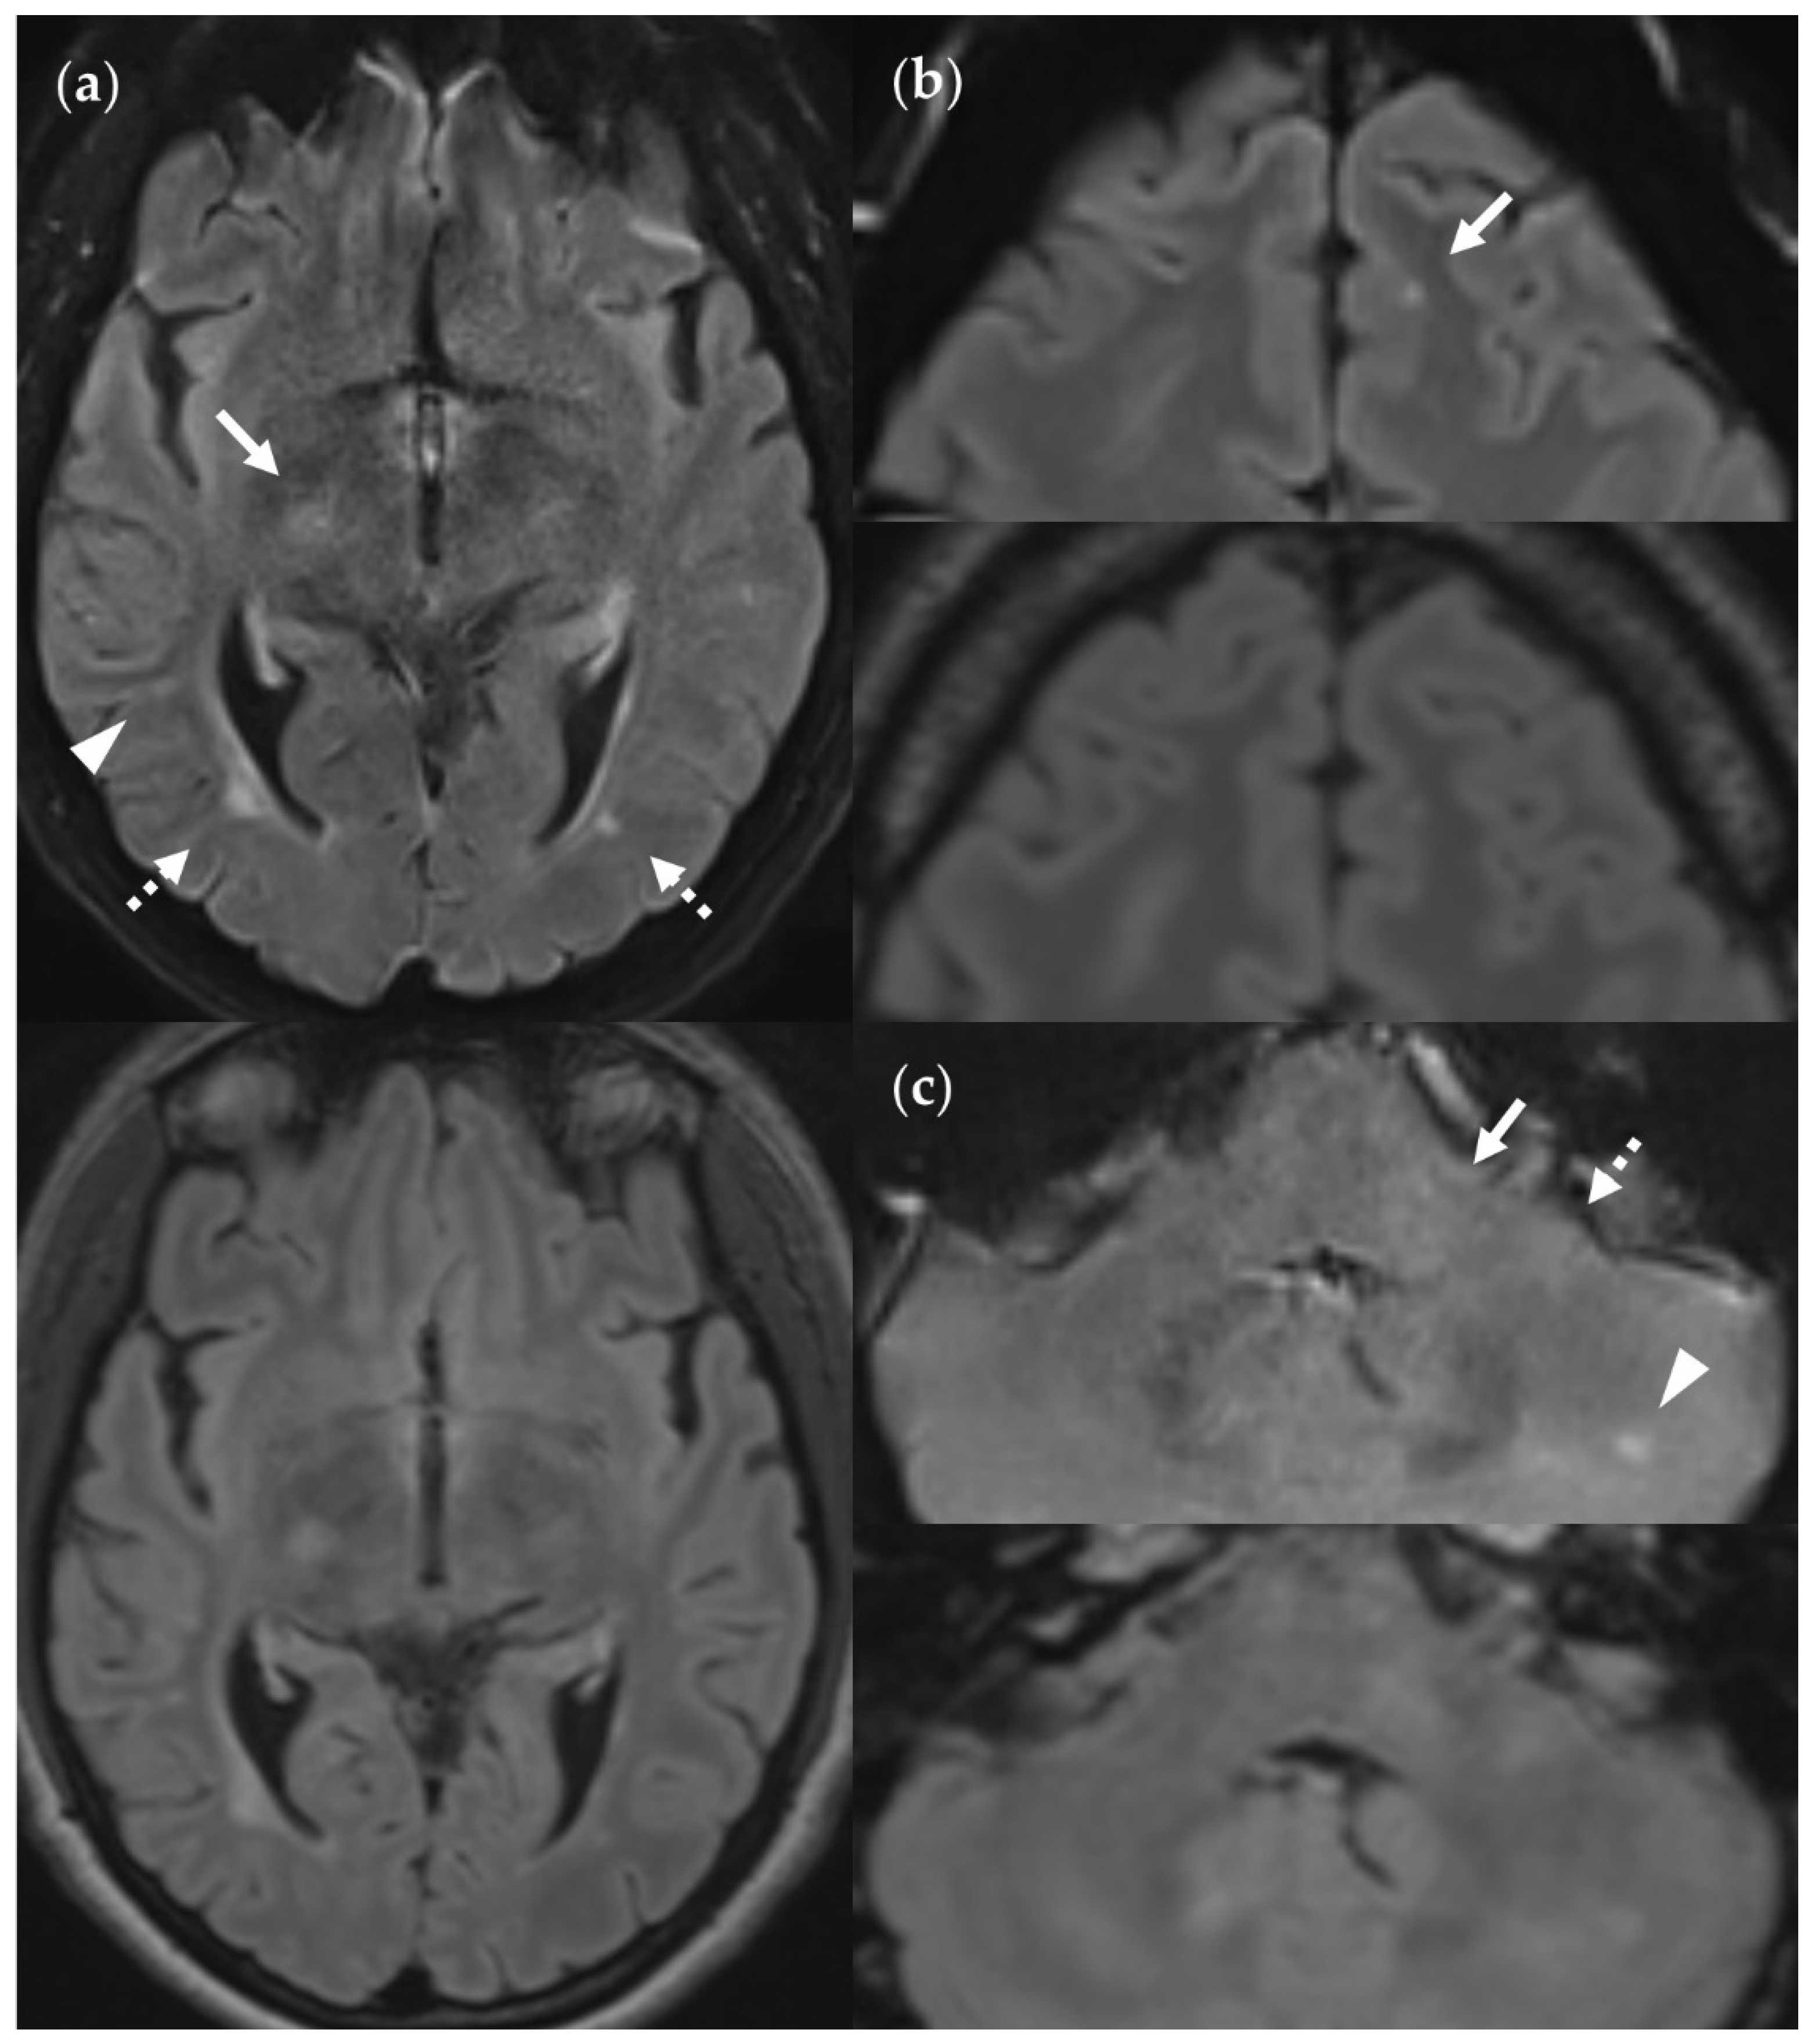

4.4. Considerations on Ratings for Lesion Conspicuity in FLAIRUF

4.5. Outcomes Correlated with Technical Features